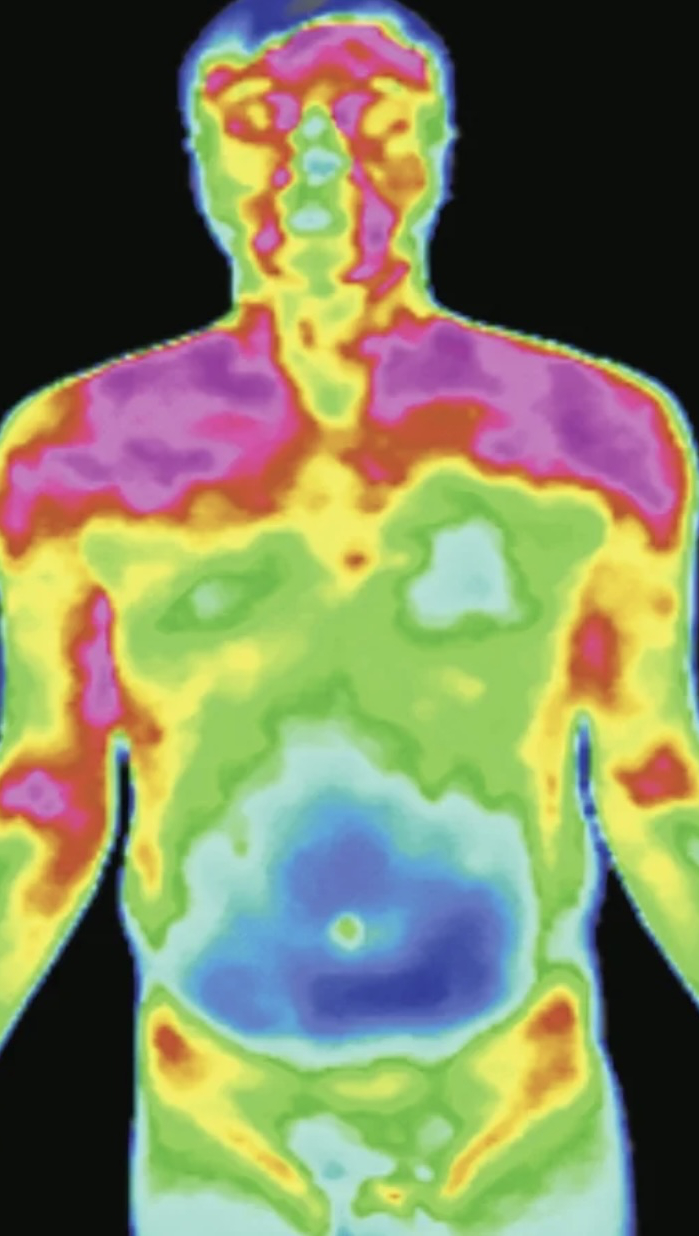

不同的中医证候分型在红外热成像仪上有明显差异,红外热成像技术进行体质测评,与现行的体质量表法评估相比,为中医临床辨证分型提供了直观的、可视化的证据。

与平和体质相比,可发现阴虚体质人群多见头面高热,尤以面颊部为要,面颊两侧温度大致对称;

气郁体质人群多见额头部高热或出现“睡眠线”,可出现一侧或单侧;

阳虚体质为阳虚失于温煦之体,常见胃脘、腰膝背部怕冷,腹部凉偏离;

痰湿体质为水液代谢失常之体,痰湿内停多见腹部肥满,有脂肪堆积的地方见低温区;

特禀体质包含过敏体质,累及全身免疫系统,代谢紊乱,可见全身花斑样改变。

根据实验结果拟提取的红外热成像特征敏感区域如下:阴虚体质,面颊高温;气郁体质,额部睡眠线;阳虚体质,胃脘部低温区;痰湿体质,腹部低温;特禀体质,躯干花斑样改变等。